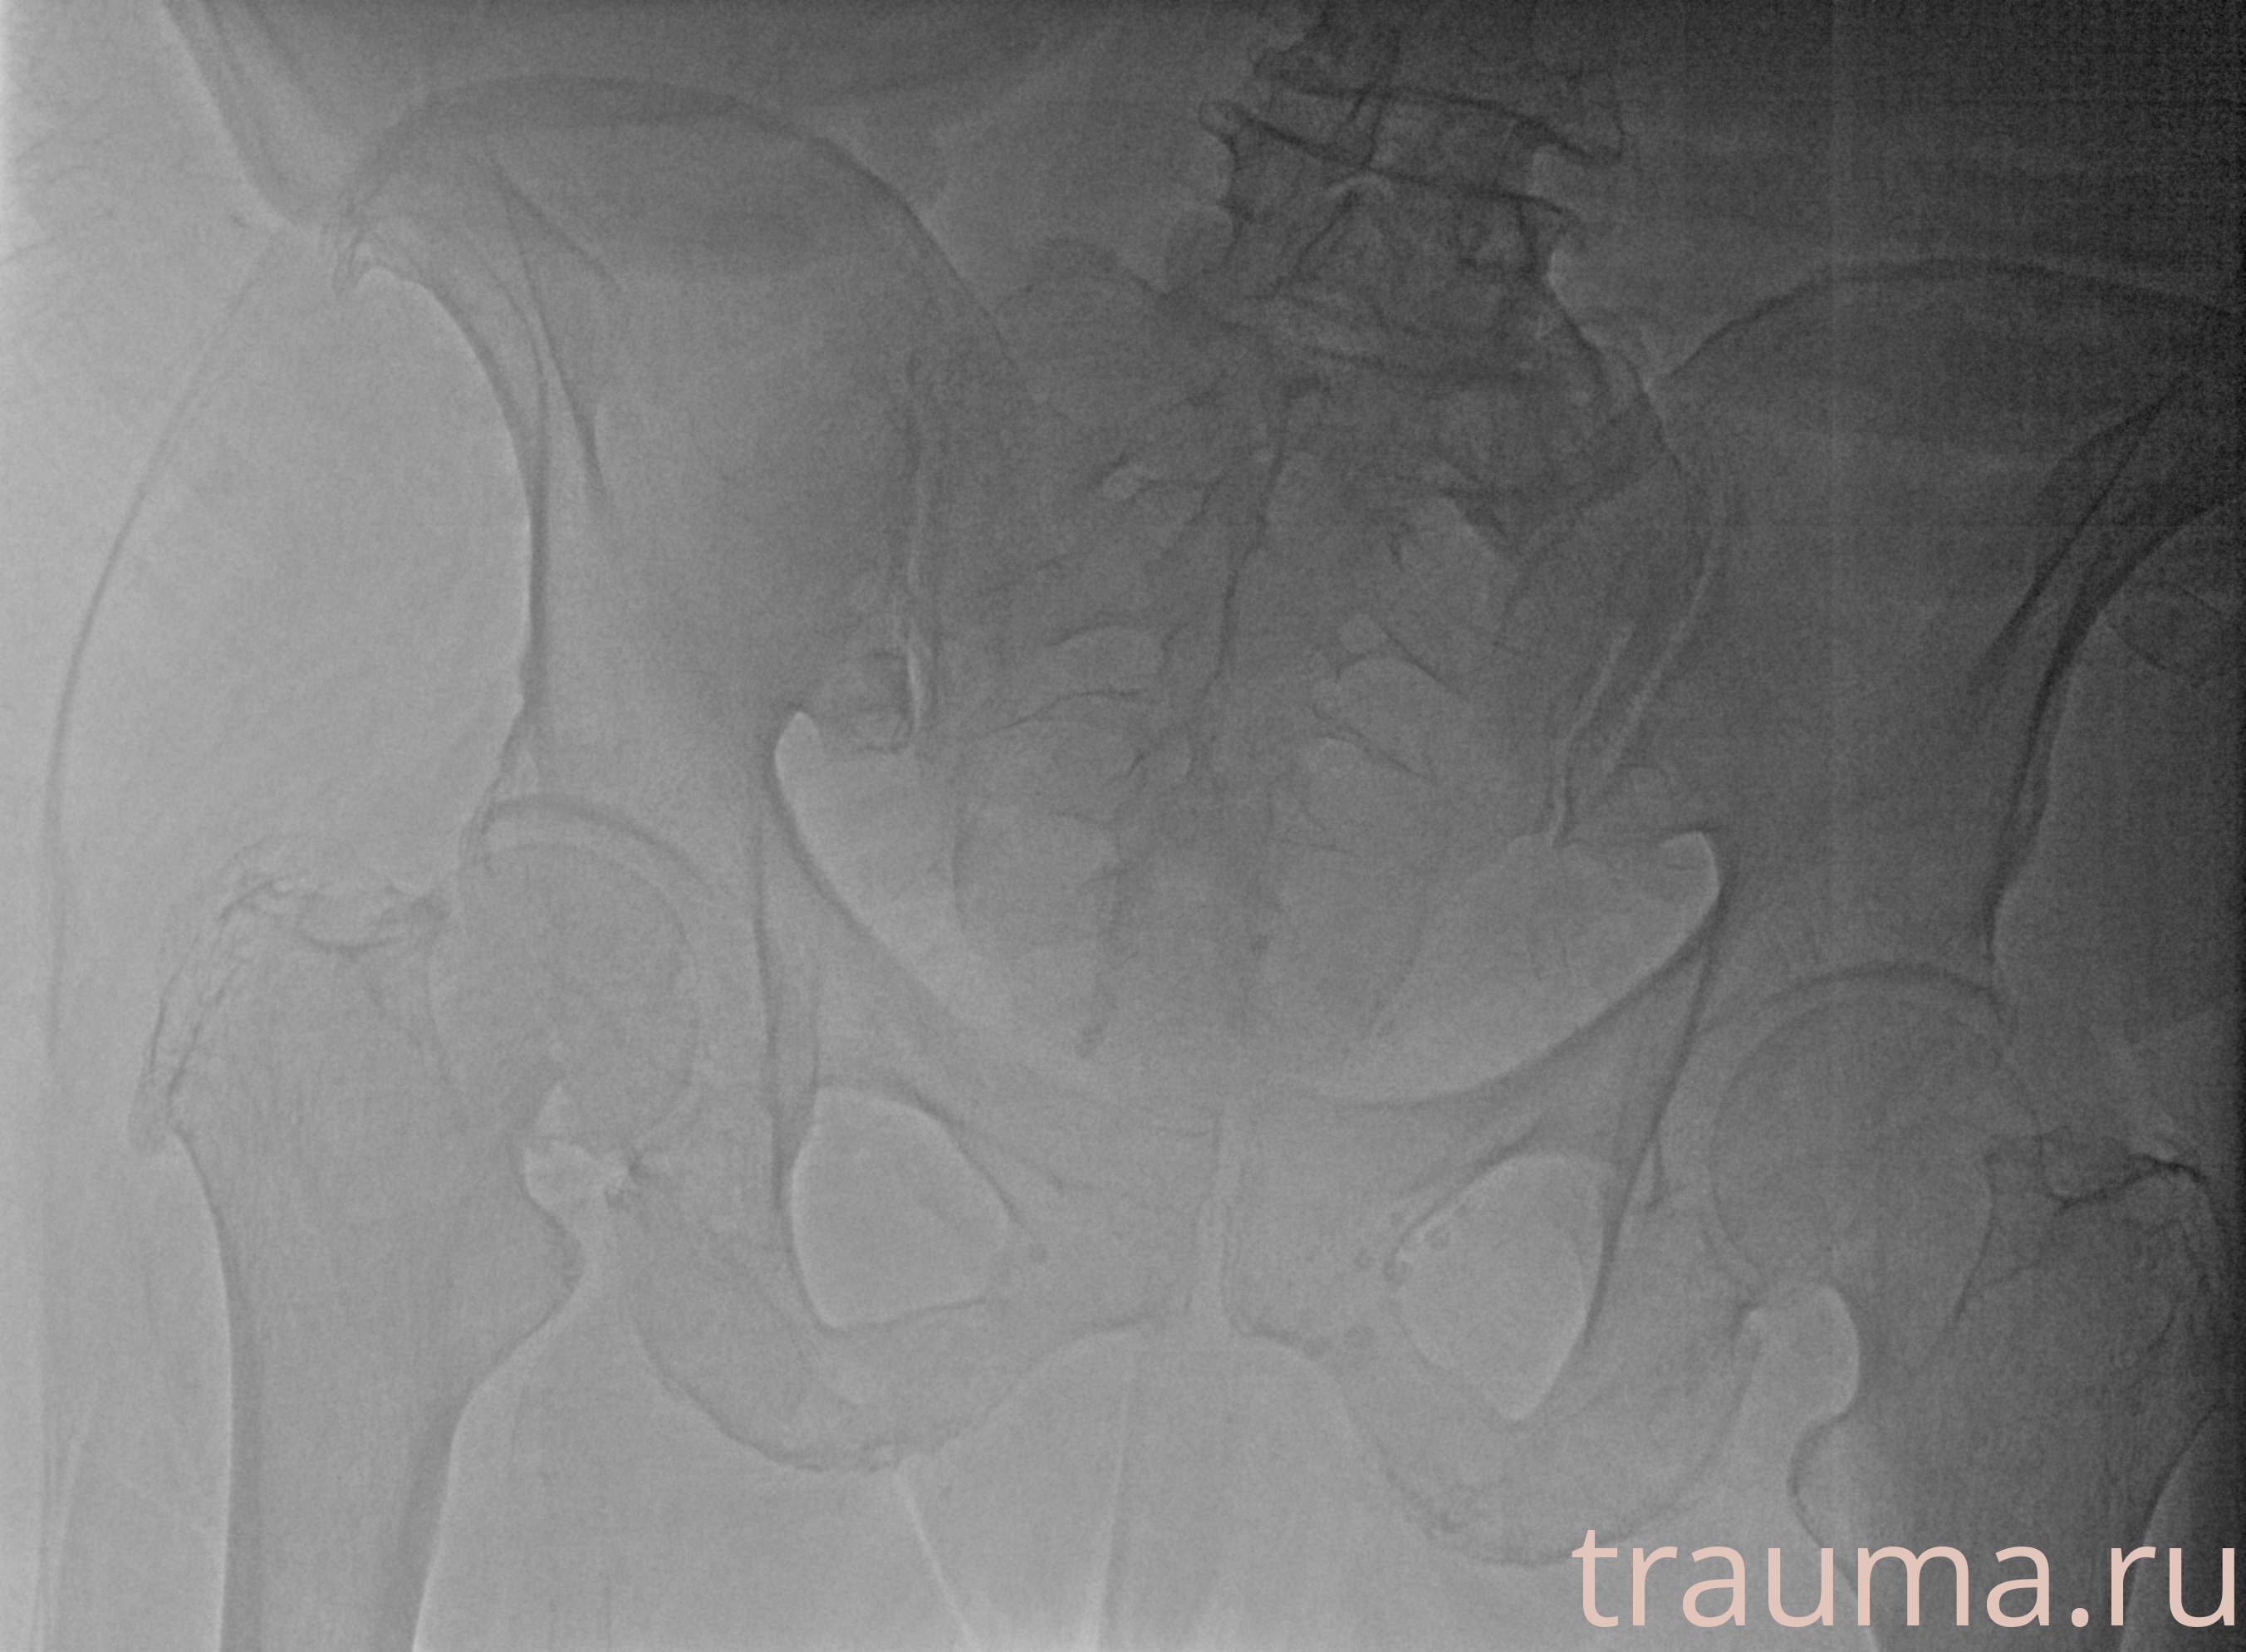

Рентгенограммы

Рентген на дому: по вашему адресу приезжает врач-рентгенолог, травматолог-ортопед с мобильным рентгеновским аппаратом, проводит диагностику травмы или заболевания, делает необходимые рентгенограммы, дает рекомендации по дальнейшему лечению. Получить качественные снимки в домашних условиях возможно благодаря уникальной методике, разработанной МосРентген Центром для института  Склифосовского